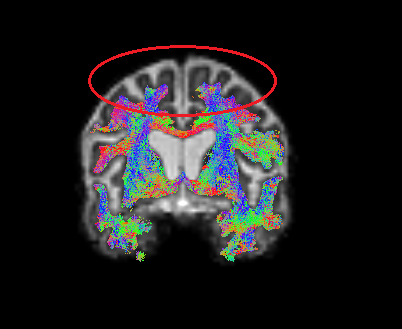

The overall segmentation in T1 space as well as after registration to DWI space looks good, however, in the circled region, grey matter appears overestimated:

In the ACT-based tractography streamlines seem to terminate incorrectly in that region:

This issue is consistently present in subjects from one study center but is not observed in data from other centers processed with the same pipeline. Could this be related to reduced T1 contrast in that region? Do you have suggestions on how to improve the segmentation in such cases?